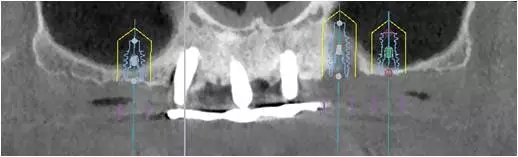

2、增加上頜種植體數(shù)量,分別與16、25、26植入3顆,行6顆種植體支撐的常規(guī)種植固定義齒修復(fù)(圖7)。16、25、26區(qū)剩余骨高度嚴(yán)重不足是該方案的不利方面,存在因需要上頜竇底提升手術(shù)所帶來的相應(yīng)手術(shù)風(fēng)險。但是,上頜竇底提升術(shù)是一個成熟、可靠的技術(shù)方法,經(jīng)過與患者充分溝通,最終選擇了這一方案。

圖7